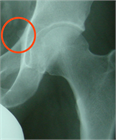

1. 単純X線撮影と読影のポイントを追加し、大腿骨寛骨臼インピンジメント(FAI)の疫学・関節症性変化への進行に関する最新の文献を参考に加筆した。

1. Cam変形は変形性股関節症の発生の危険因子になる(推奨度1、エビデンスランクC、J)